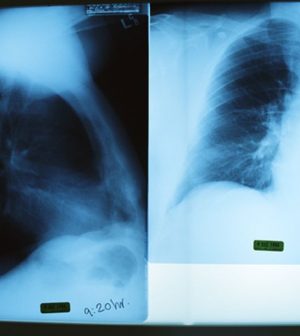

When cancer specialists prepare to perform radiation therapy, they scan the patient’s body to determine the exact position and size of the tumor, the researchers explained. Before every treatment that follows, more images are used to ensure that the patient and the tumor are in the same position.

For the study, the researchers recruited 780 patients undergoing radiation therapy for non-small cell lung cancer. For each treatment, patients were positioned on the machines and an image was taken to ensure they were lying within 5 millimeters (mm) of their original position.

The researchers used the images to assess how precisely the radiation was delivered, and to determine if it shifted closer or farther away from the heart.